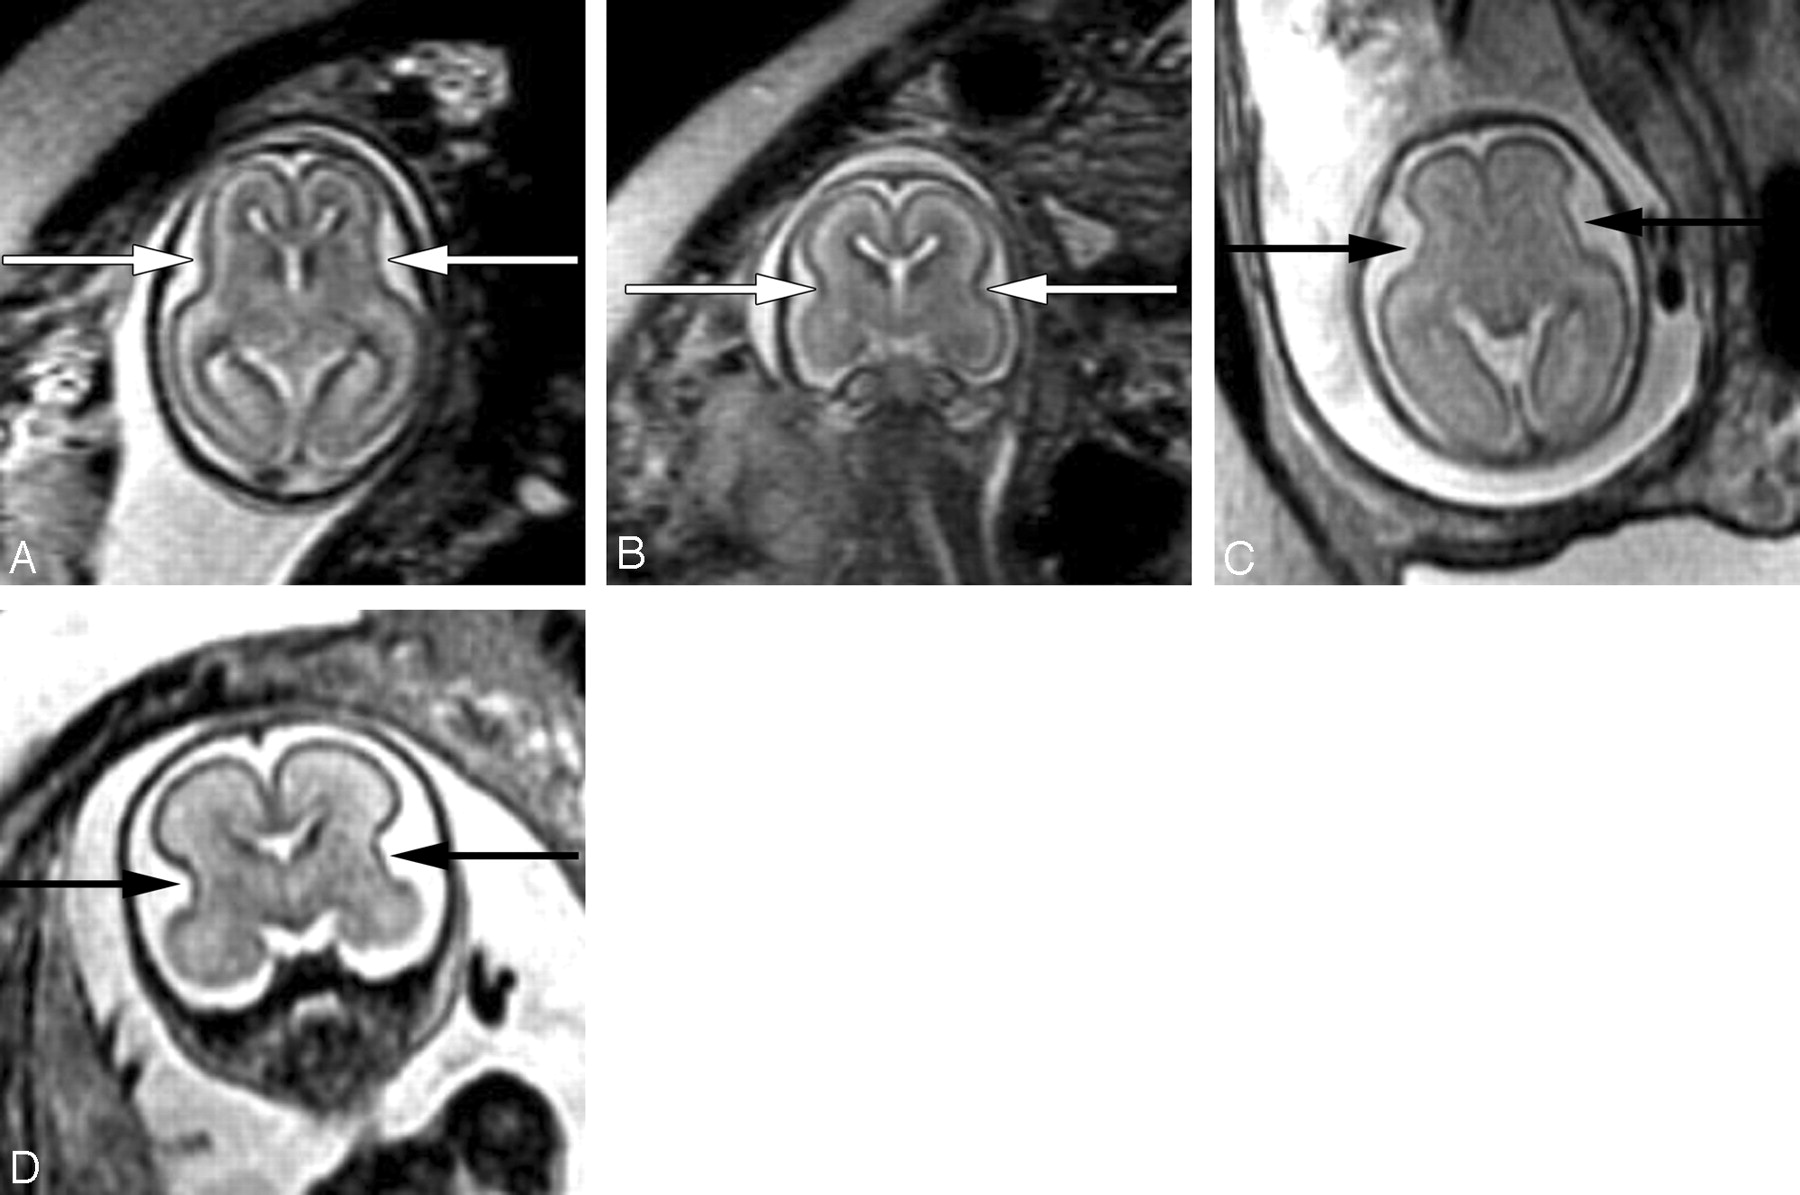

The sylvian fissures are visible on fetal MR imaging before gestational week 18. They initially appear as smooth, curved, wide infoldings on the surface of the brain. At gestational week 23, they appear more angular and less smooth as a result of increased formation of the anterior and posterior operculum (Fig 3). The shape of the sylvian fissures in early phases of development is best assessed on coronal and axial images. Late maturation of the sylvian fissure is a sign of abnormal development.

Axial (A) and coronal (B) SS-FSE T2-weighted image demonstrates smooth shallow appearance of the Sylvian fissures at gestational week 20. At gestational week 23, the Sylvian fissures (arrows) appear more angled on both axial (C) and coronal (D) images.